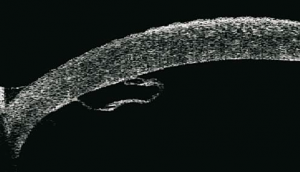

Ultrasound Biomicroscopy

The inability to visualize the anterior segment by conventional ultrasound B-Scan and high resolution radiologic images led to a shift towards alternate imaging modalities. The first practical Ultrasound biomicroscopy (UBM) system was developed by Foster and Pavlin in the early 1990s. UBM is an imaging technique that uses high-frequency (35-50MHz) sound waves to produce high-resolution, cross-sectional images of the anterior segment to a depth of approximately 5 mm.[8] Thus UBM is suitable for detailed imaging of anterior segment anatomy and pathology, including the cornea, irido-corneal angle, anterior chamber, iris, ciliary body and lens.[3]

UBM also has a great value in the presence of corneal pathology such as edema, keratoconus or corneal scars. It can demonstrate disruption of the intraocular structures as seen in iridodialysis, angle recession, cyclodialysis, zonular rupture, scleral laceration, foreign body and epithelial ingrowth, irrespective of the opaque media, and can provide evidence for treatment.[3]

An additional advantage of UBM is that images are acquired in real time with mobility of various structures visualized in situ. High frequency (50 MHZ) ultrasound also identify the exact loation, size, and nature of a foreign body along with the appearance of surrounding tissue much better than conventional low frequency (10 MHZ) ultrasound.[9] Although CT is superior for detecting foreign bodies, ultrasound is more useful for localizing foreign bodies relative to the ocular coats. It is also superior to CT in showing extent of ocular damage associated with an IOFB. UBM is also useful for detection and localization of small superficial non-metallic foreign bodies that are usually missed on CT and conventional USG.[10] UBM can be used to accurately assess the zonules. Zonular defects diagnosed by UBM in cases of traumatic cataract allows the ophthalmic surgeon to plan preoperatively to prevent vitreous loss or nucleus drop in the vitreous cavity [11]